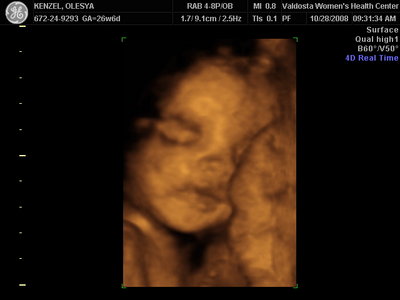

Ксюнь, а мы вообще не поняли. Она на всех фотках разная, да еще размытость такая. Пуповина то на носу болталась, то руками-ногами закрывалась. Главное что четкости нет совсем. Лоб у мужа тоже большой, а носы и губы зачастую на 3Д-4Д выходят разамазанно-пухло-приплюснутыми Поставлю для наглядности фотку моей средней-Джианки с 3Д УЗИ, там видно черты намного лучше и она на себя ту похожа сейчас, хотя родилась мне совсем на фото УЗИ не казалась похожей.

| Вложения: |

KENZEL,OLESYA_3.JPG [ 56.84 КБ | Просмотров: 1428 ]

Катюш, какой прикольный бутузик ! Олесь, после фотки средней - точно прям похожи!